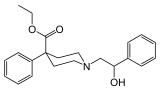

Phenylpiperidines

- Pethidine (meperidine)

The first fully synthetic opioid was meperidine (later demerol), found serendipitously by German chemist Otto Eisleb (or Eislib) at IG Farben in 1932.[228] Meperidine was the first opiate to have a structure unrelated to morphine, but with opiate-like properties.[199] Its analgesic effects were discovered by Otto Schaumann in 1939.[228] Gustav Ehrhart and Max Bockmühl, also at IG Farben, built on the work of Eisleb and Schaumann. They developed "Hoechst 10820" (later methadone) around 1937.[230] In 1959 the Belgian physician Paul Janssen developed fentanyl, a synthetic drug with 30 to 50 times the potency of heroin.[211][231] Nearly 150 synthetic opioids are now known.[228]